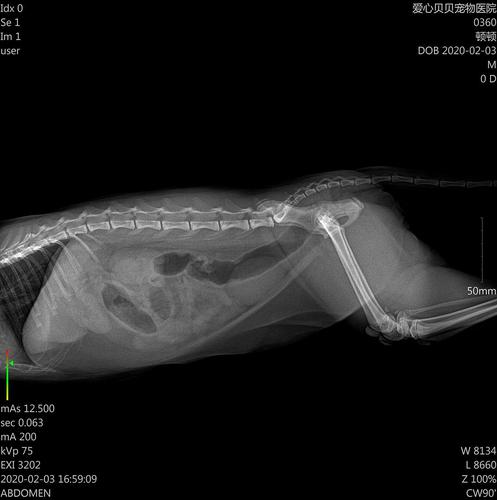

猫咪在45天左右就可以做B超观察胎儿状态。B超的费用会因为地区不同而费用不同,越发达的地方可能价钱越贵,大概费用在120-200左右。B超是很有必要做的,能够辨别胎儿是否健康,若是想要看胎儿数量和胎位需要借助X光或DR,费用在150-300之间。

猫咪在45天左右就可以做B超观察胎儿状态。B超的费用会因为地区不同而费用不同,越发达的地方可能价钱越贵,大概费用在120-200左右。B超是很有必要做的,能够辨别胎儿是否健康,若是想要看胎儿数量和胎位需要借助X光或DR,费用在150-300之间。养猫一般一年成本多少钱呢 养一只猫一年的成本大概是3400元。

要想确认猫咪是否怀孕,最直接的办法就是带其到医院做b超。宠物医院b超的费用受多种因素的影响,都是不一样的,但一般都在120-200元之间。猫咪在45天左右就可以做B超观察胎儿状态。B超的费用会因为地区不同而费用不同,越发达的地方可能价钱越贵,大概费用在120-200左右。